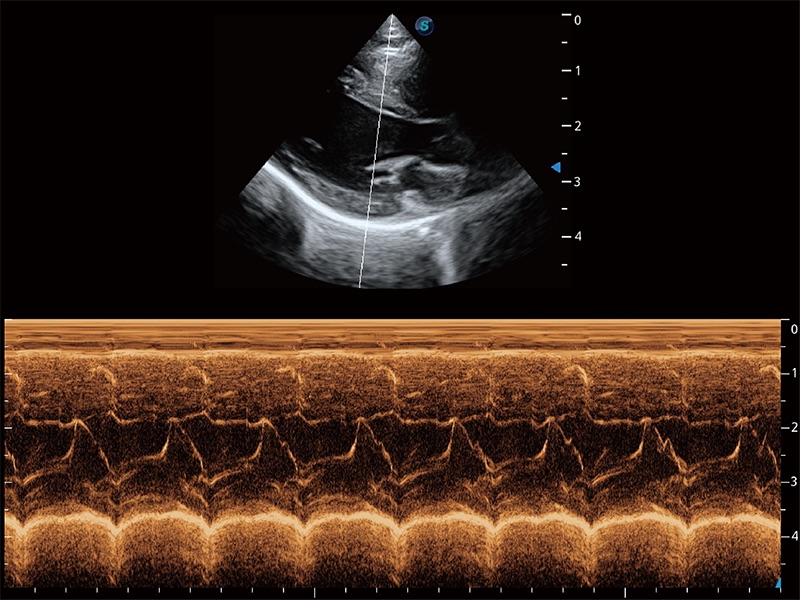

优异的基础图像

ProPet 80 全新的动物超声智能软件和丰富的探头群,为动物医生提供了高清晰度和精细分辨率的图像,无论在宠物、马科、畜牧还是实验室动物等应用中都可以轻松应对,为您的日常工作带来满意的体验。

(犬)四腔心MQA

(猫)二尖瓣M型

• AMM 解剖M型

通过360度任意调节3条M型取样线,在同一心动周期上观察心脏不同位置的运动曲线,得到准确的心功能测量数据,有效评估心肌运动及左心室功能。